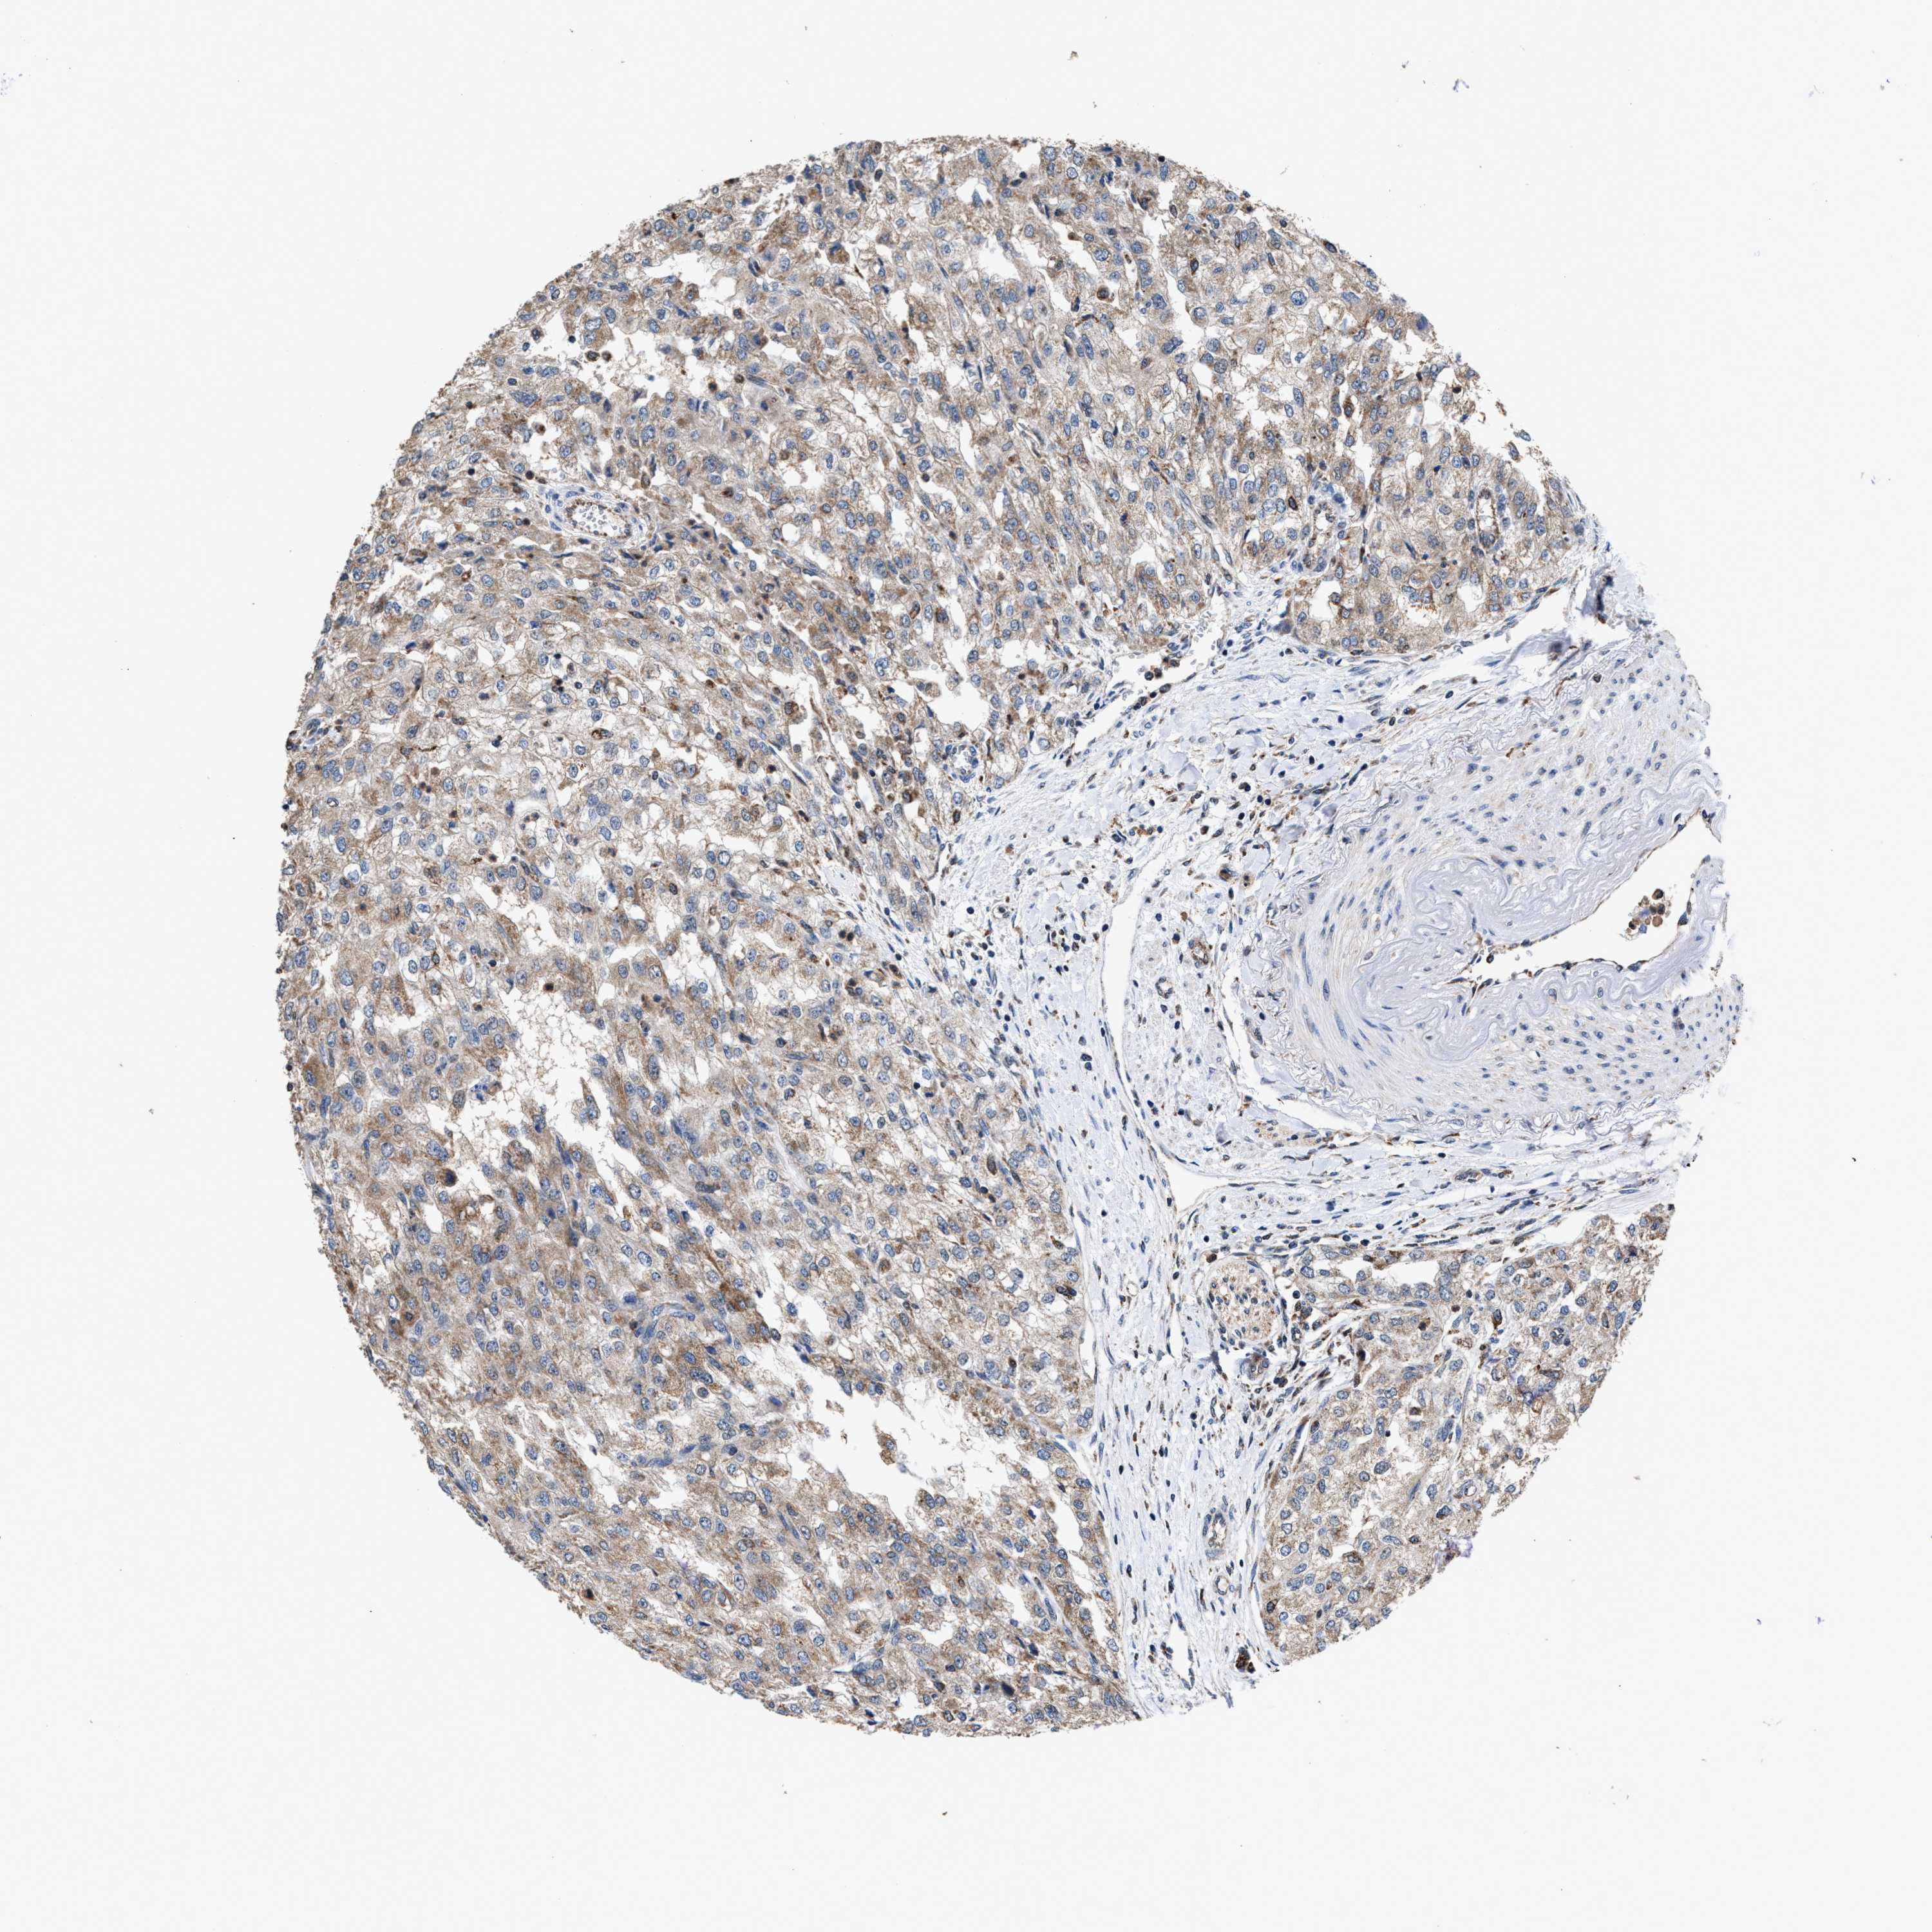

KIDNEY RENAL CLEAR CELL CARCINOMA (TCGA) - Interactive survival scatter ploti

The Survival Scatter plot shows the clinical status (i.e. dead or alive) for all individuals in the patient cohort, based on the same data that underlies the corresponding Kaplan-Meier plots. Patients that are alive at last time for follow-up are shown in blue and patients who have died during the study are shown in red.

The x-axis shows the expression levels (FPKM) of the investigated gene in the tumor tissue at the time of diagnosis. The y-axis shows the follow-up time after diagnosis (years). Both axes are complimented with kernel density curves demonstrating the data density over the axes. The top density plot shows the expression levels (FPKM) distribution among dead (red) and alive patients (blue). The right density plot shows the data density of the survived years of dead patients with high and low expression levels respectively, stratified using the cutoff indicated by the vertical dashed line through the Survival Scatter plot. This cutoff is automatically defined based on the FPKM cutoff that minimizes the p-score. The cutoff can be changed by dragging the vertical line or by entering a cutoff value in the square labeled "Current cut-off".

Under the Survival Scatter plot the p-score landscape (black curve; left axis) is shown together with dead median separation (red curve; right axis). Dead median separation is the difference in median mRNA expression between patients who have died with high and low expression, respectively. It is calculated as follows: median FPKM expression of dead patients with high expression - median FPKM expression of dead patients with low expression. This is intended to aid the user in visually exploring custom cutoffs and the associated p-scores and dead median separation.

Individual patient data is displayed and can be filtered by clicking on one or more of the category buttons on the top of the page. Categories describing expression level and patient information include: high, low, alive, dead, female, male and tumor stages. The scale of the x-axis can be toggled between linear and log-scale by clicking on the "x log" button. Mouse-over function shows TCGA ID, patient information and mRNA expression (FPKM) for each patient.

& Survival analysisi

Kaplan-Meier plots summarize results from analysis of correlation between mRNA expression level and patient survival. Patients were divided based on level of expression into one of the two groups "low" (under cut off) or "high" (over cut off). X-axis shows time for survival (years) and y-axis shows the probability of survival, where 1.0 corresponds to 100 percent.

ACLY is potential prognostic, high expression is favorable in Kidney Renal Clear Cell Carcinoma (TCGA)

: 197.59

Average pTPM 159.7

Number of samples 521